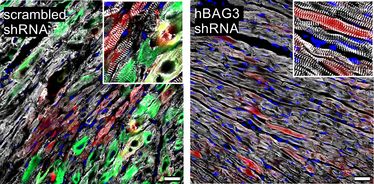

Tatsächlich gibt es Methoden, einzelne Gene in ihrer Aktivität gezielt zu hemmen. Eine davon wurde genutzt, um die kranken Mäuse zu behandeln - die so therapierten Tiere zeigten dann deutlich weniger Symptome. Ob sich dieser Ansatz auf den Menschen übertragen lässt, ist allerdings noch Gegenstand weiterer Forschung.

Das Institut für Physiologie II der Universität Münster brachte vor allem Expertise bei der Analyse der Substruktur von Muskelzellen in die Studie ein. „Die Kooperation mit den Kollegen in Bonn passt exakt zu unseren Forschungsgebieten, da wir uns für die genetischen Ursachen von Herz- und Muskelerkrankungen und deren funktionale Auswirkungen interessieren“, freut sich Institutsdirektor Prof. Wolfgang Linke über die erfolgreiche Studie. „Ich hoffe, dass unsere Arbeit hilft, den von einer BAG3-Mutation schwer betroffenen Patienten in der Zukunft eine bessere Behandlungsperspektive zu geben.“